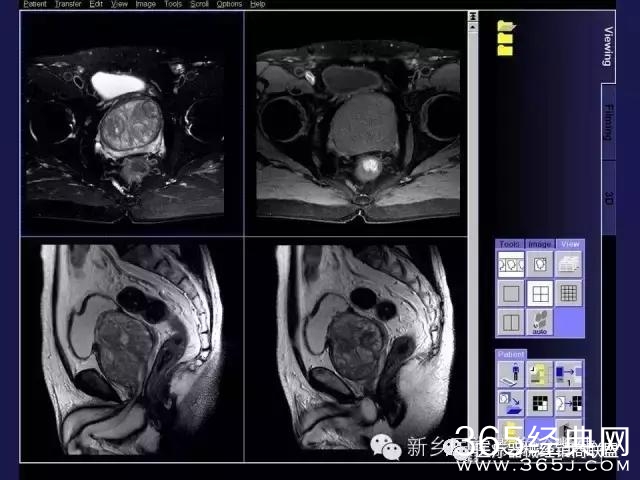

CT、MRI很难?NO,今日我们一起来学习一下如何读CT、MRI!

内行看门道:

整整90张图